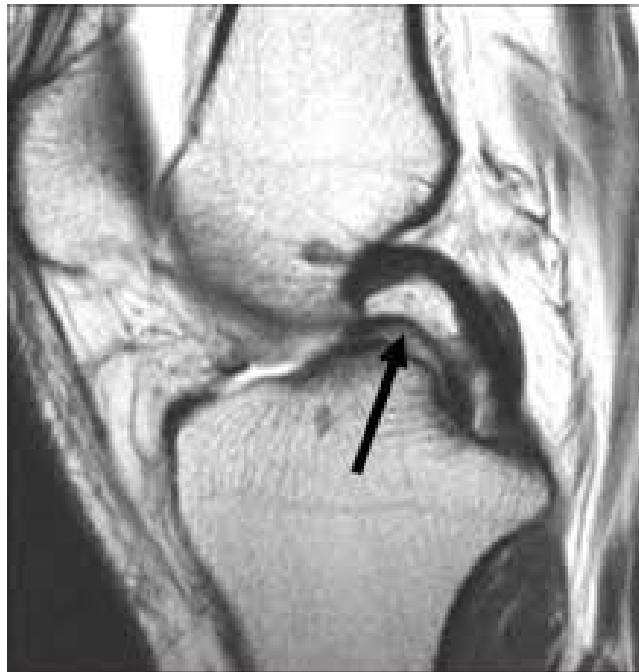

| ACL & PCL: Anterior/Posterior Drawer Test OR Lachman’s test OR Pivot Shift test | Assess integrity of Anterior and Posterior Cruciate Ligaments specifically | Anterior/Posterior Drawer Test: Lachman’s test: ![]() | Excessive anterior or posterior translation of the tibia, indicating ACL or PCL injury | |

| Meniscus: McMurry’s test OR Medial & Lateral joint tenderness Apley grinding test | Assess for meniscal tears | McMurry’s test: Apley grinding test: ![]() | Click, thud, or pain during knee flexion, extension, and rotation during McMurray’s; pain during compression and rotation during Apley’s. | |